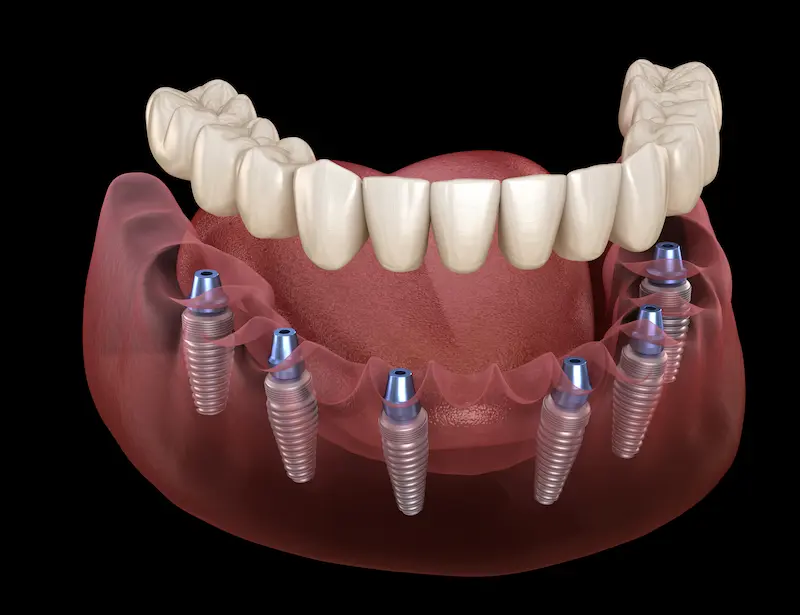

تقوم فكرة زراعة الأسنان All on 6 على وضع ستة غرسات (زرعات سنية) في عظم الفك لتحمل طقمًا ثابتًا من الأسنان الصناعية، ما يسمح بتعويض كامل الأسنان المفقودة في الفك العلوي أو السفلي. وتُستخدم هذه التقنية عادةً مع المرضى الذين خسروا غالبية أسنانهم بسبب التسوس الشديد أو الأمراض اللثوية أو الحوادث. يختلف “All on 6” عن بعض الأنواع الأخرى من الأنظمة المشابهة (مثل All on 4) في أنه يستخدم ست زرعات بدلًا من أربع، ما يوفّر:

- ثباتية أكبر وتحمّل لقوى المضغ: إذ تسمح بعض المزروعات الإضافية بتوزيع أفضل للضغط على عظم الفك.

- مرونة في التصميم: قد يتيح هذا النظام خيارات أكثر في تصميم الجسر أو البدلة، خاصةً مع اختلاف أشكال عظم الفك لدى المرضى.

- قابلية أكبر للتعامل مع مشاكل العظم: في بعض الحالات التي لا يلائمها All on 4 بشكل مثالي، يمكن للنظام القائم على 6 زرعات توفير الدعم اللازم من خلال توزيع الغرسات في مواضع مختلفة.

- البدء بالإجراء: بعد التخدير الموضعي أو الكامل (حسب تفضيل المريض وخطة العيادة)، يُجري الطبيب شقوقًا بسيطة في اللثة، ثم يغرس 6 زرعات مصنوعة عادةً من التيتانيوم عالي التوافق الحيوي. إذا كانت الحالة تسمح، يمكن وضع تركيبة مؤقتة بنفس اليوم أو بعد أيام قليلة (ما يعرف بـزراعة الأسنان الفورية).